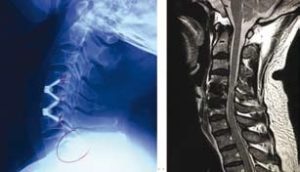

55歳的陸先生是位工程師,在2016年11月來求診,兩年來他手部 麻木 痺痛,尤其是右手拇指及二指,後來更出現 手部乏力 、走路時 腳軟 無力的情況。兩年來看了不同科的西醫及中醫,亦接受了 物理治療 及 脊醫 的保守治療。臨床的神經反射檢查顯示陸先生有頸椎中樞神經嚴重受壓的可能,隨後的 磁力共振 醫學造影確診了頸椎第四、五及第五、六節出現嚴重退化及 椎間盤突出 ,而且嚴重壓向脊髓中樞神經,脊髓神經有變形、扁平及 水腫 現象。

陸先生最後聽從醫生的醫學意見,入院進行了四小時的神經外科微創手術 ─ 頸椎前路椎間盤切除及椎體融合術,手術目的是為脊髓中樞神經減壓及鞏固頸椎的穩定性。手術後陸先生臥床休息一晚,第二天早上他發現四肢已經沒有麻木痺痛的感覺,四肢肌肉力度亦有明顯改善。在醫生的監察下他下床走動,發覺雙腳站立地面上時的感覺比手術前實在而且穩健得多,走起路來雙腳力度及步履明顯進步同時相當平穩。從 X-光 及 磁力共振 觀察,頸椎第四、五及第五、六節脊髓受壓程度已大大改善。陸先生當天下午,即手術後24小時便出院回家了。